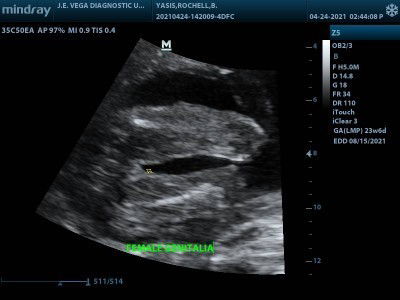

Baby Girl through Through Congenital Anomaly Scan, may chance ba na magkamali gender ni baby?

We want a baby girl and God gave us. Nag pa CAS ako on my 23rd week, nakakaloka officemate ko sinasabi na lalake daw, mababago pa daw to, sabi ko nga na hindi naman to normal na ultrasound. Porket nag iba talaga itsura ko, dumami acne ko and tinatamad ako mag ayos na din dahil nga sa acne ko. Napaisip naman ako, hmps kainis sya mas magaling pa sa sonographer. Hahaha #1stimemom #firstbaby #pregnancy